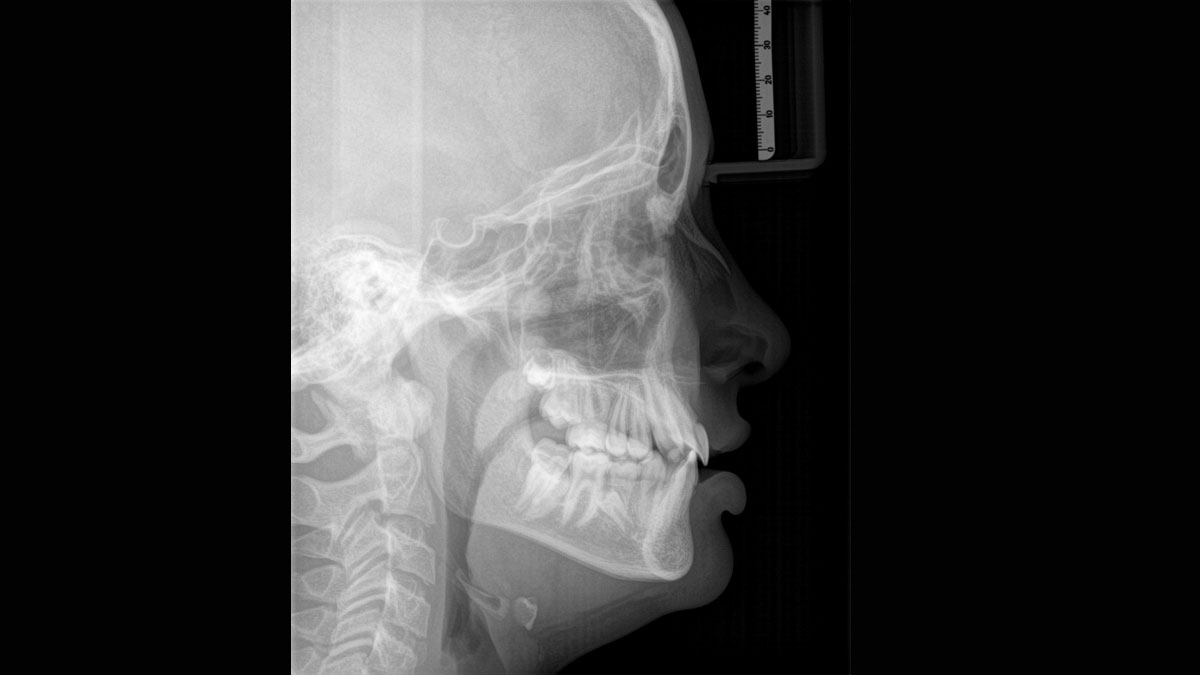

Los numerosos tamaños de volumen garantizan la flexibilidad en la práctica diaria. Examine un área precisa o evalúe la dentición completa, lo que incluye las ATM

Para obtener imágenes panorámicas excepcionales con alta nitidez. Puede elegir un brazo cefalométrico derecho o izquierdo opcional, que puede reacondicionarse en cualquier momento